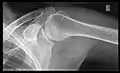

Shoulders

_X-ray_of_a_normal_shoulder.jpg.webp)

These include:

- AP-projection 40° posterior oblique after Grashey

The body has to be rotated about 30 to 45 degrees towards the shoulder to be imaged, and the standing or sitting patient lets the arm hang. This method reveals the joint gap and the vertical alignment towards the socket.[17]

- Transaxillary projection

The arm should be abducted 80 to 100 degrees. This method reveals:[17]

- The horizontal alignment of the humerus head in respect to the socket, and the lateral clavicle in respect to the acromion.

- Lesions of the anterior and posterior socket border or of the tuberculum minus.

- The eventual non-closure of the acromial apophysis.

- The coraco-humeral interval

- Y-projection

The lateral contour of the shoulder should be positioned in front of the film in a way that the longitudinal axis of the scapula continues parallel to the path of the rays. This method reveals:[17]

- The horizontal centralization of the humerus head and socket.

- The osseous margins of the coraco-acromial arch and hence the supraspinatus outlet canal.

- The shape of the acromion

This projection has a low tolerance for errors and accordingly needs proper execution.[17] The Y-projection can be traced back to Wijnblath’s 1933 published cavitas-en-face projection.[18]

In the UK, the standard projections of the shoulder are AP and Lateral Scapula or Axillary Projection.[15]